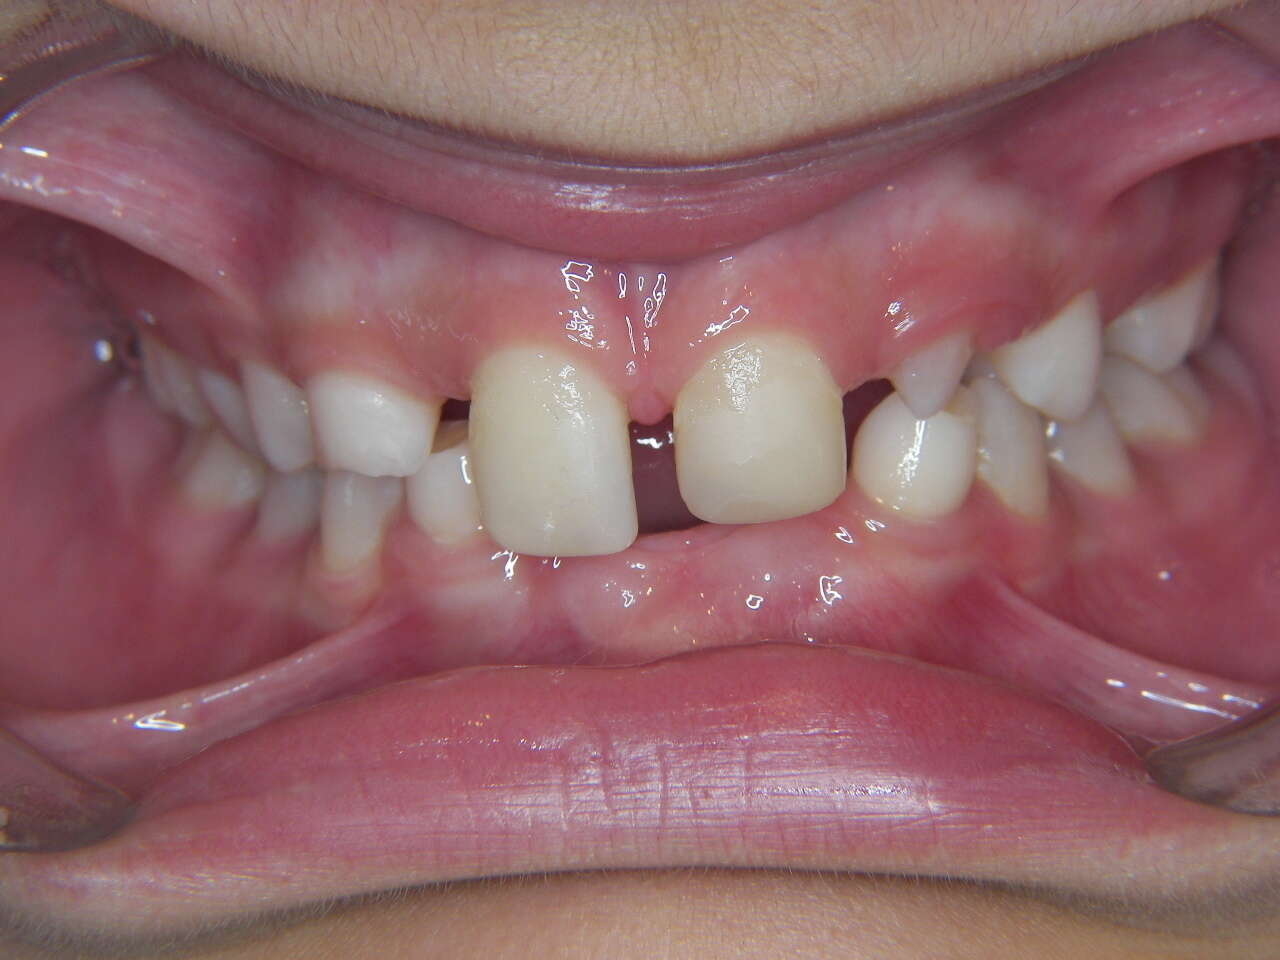

Polyagénésies : dents qui n'existent pas

Intrabuccale face